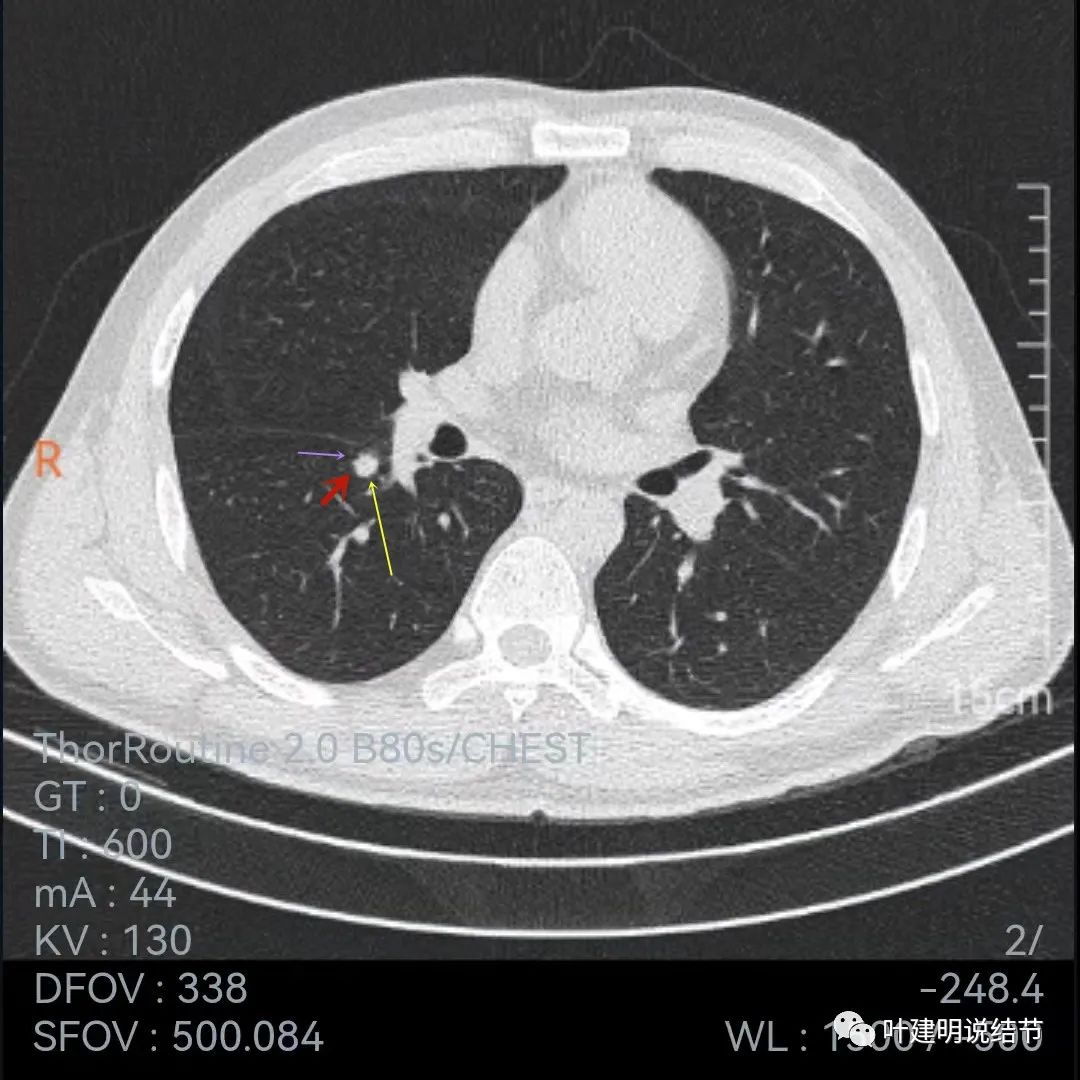

再来看薄层的,今年的薄层是1毫米一层的,去年是2毫米:

病灶胸膜凹陷更明显了,边缘不太平整(紫色箭头)

胸膜牵拉,伴病灶中间密度稍低

病灶膨胀性不够,感觉刺突相对较长,中间密度略低,边缘向内凹

上图黄色箭头示病灶中间密度要略低于周边部位,这与肉芽肿较为符合

整体还病灶似有进展,形态略有变化,但说典型的恶性样子好像又不太像。